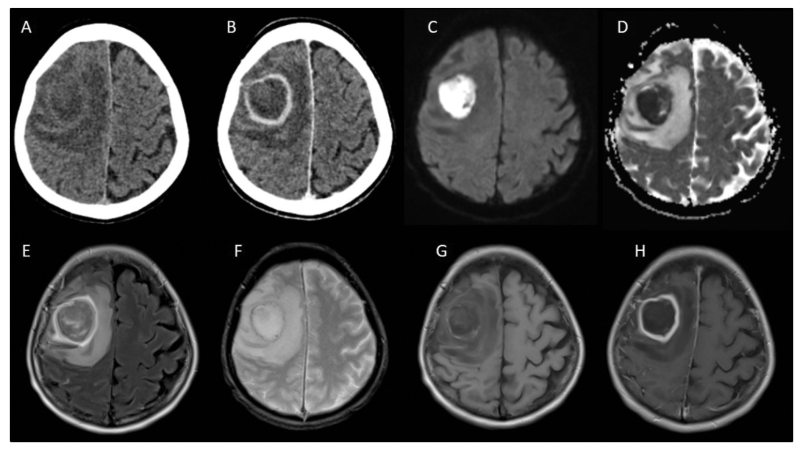

CT: C- (A) et C+ (B): abcès frontal droit

IRM: DWI (C) ADC (D), FLAIR (E), T2 EG (G) et T1 C+ (H): abcès frontal droit